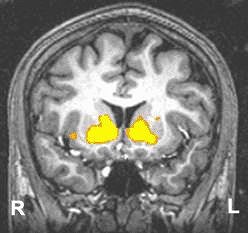

Functional MRI detects regions in the brain where extra oxygen in the blood flows in response to events in the environment. The scans depict the ventral striatum, known to be involved in motivating organisms to seek natural (such as food and sex) and artificial (such as street drugs) rewards. In young adults (above), both sides of the ventral striatum were robustly activated by the prospect of responding to win a reward. In adolescents (below), the ventral striatum showed less activation. Images and caption courtesy of NIAAA’s Laboratory of Clinical Studies Section of Brain Electrophysiology and Imaging.

According to the results, the adolescents and the young adults performed similarly on the MID task, with an overall hit rate of 69.9%. Both groups reported greater happiness at winning and greater fearfulness at losing based on the answers to a questionnaire. With regard to anticipation of gain, both showed bilateral activation of the nucleus accumbens (NAcc). Gain versus non-gain outcomes also stimulated several portions of the prefrontal cortex and the putamen bilaterally.

However, the results indicated reduced gain anticipation activation in the right ventral striatum (VS) of the adolescents, centered in the NAcc. This right-selective deficit in recruitment of the VS may reflect developmental deficits in attention control in the adolescents during the MID task, the authors reported. In comparison, the adults demonstrated orderly activation in the right NAcc, especially as the dollar amounts increased.

"This finding provides support for an adolescent VS activation deficient (in) adolescent risky behavior, in which adolescents may seek more extreme incentives as a way of compensating for low VS activity levels," they wrote. "These data are also consistent with findings from psychosocial research that adolescents are less optimistically biased about obtaining future rewards compared with adults."